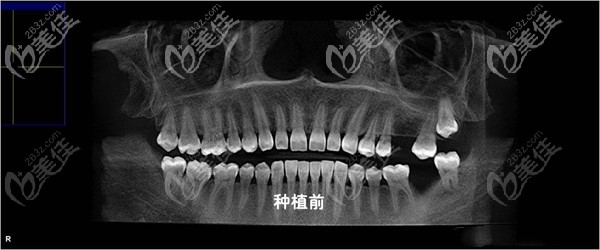

術(shù)前照片:

其實(shí),我后邊兩顆牙缺失已經(jīng)很長(zhǎng)時(shí)間了,少則也有五六年的時(shí)間吧,大體還是因?yàn)樾r(shí)候吃糖太多,不愛(ài)惜牙齒造成的。

但在去年洗牙時(shí),就發(fā)現(xiàn)缺失牙旁邊的牙齒已經(jīng)開(kāi)始傾斜,本身自己愛(ài)抽煙又再加上牙齒缺失,整個(gè)口腔環(huán)境其實(shí)一直都不好,所以,在兩個(gè)月前我決定來(lái)杭州北樂(lè)口腔做了瑞士ITI種植牙。

種植牙一般分為三個(gè)步驟,先是種上種植體,之后過(guò)三個(gè)月再來(lái)安裝基臺(tái)之后再是牙冠,而我現(xiàn)在是先植入了種植體。